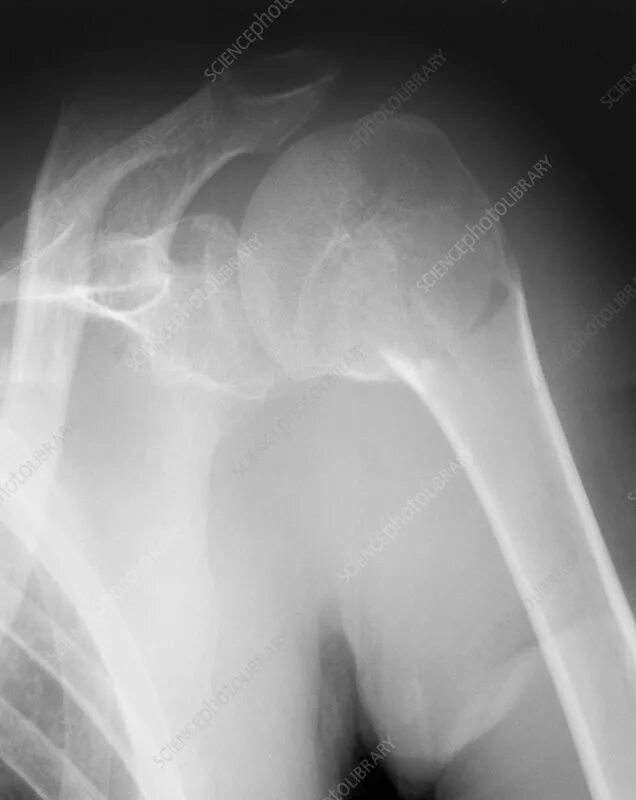

Операция при переломе шейки плеча